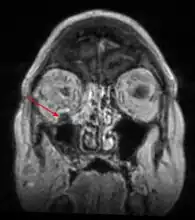

Imaging is often performed, such as CT scan of lungs and sinuses.[38] Signs on chest CT scans, such as nodules, cavities, halo signs, pleural effusion and wedge-shaped shadows, showing invasion of blood vessels may suggest a fungal infection, but does not confirm mucormycosis.[16] A reverse halo sign in a person with a blood cancer and low neutrophil count, is highly suggestive of mucormycosis.[16] CT scan images of mucormycosis can be useful to distinguish mucormycosis of the orbit and cellulitis of the orbit, but imaging may look identical to those of aspergillosis.[16] MRI may also be useful.[39]

MRI head: right sided sinus involvement extending into the orbit.